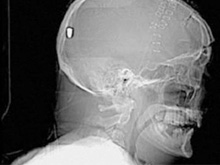

В Британии врачи нашли у пациента пулю в голове13.05.10 13:07 Прочтений новости 980 Общество В Британии у пациента, который поступил в клинику с подозрением на инсульт, врачи обнаружили пулю в голове. Но остается неизвестным, как мужчина получил ранение.Рентгеновские снимки головы показали, что в полости черепа находится инородный предмет. Мужчине сделали томографию головы, и врачи установили, что этим предметом является пуля. Как сообщается, 19 апреля 61-летний Питер Хесфорд упал во время работы у себя в саду. Позже его обнаружила жена, которая вызвала скорую. Мужчина оставался в сознании, но не мог говорить. Медики, прибывшие на место, заподозрили у Питера Хесфорда инсульт и доставили его в Больницу Уитеншо. Эксперты по баллистике, изучив снимки пациента, пришли к выводу, что пуля, застрявшая в затылочной области, могла попасть туда через глаз. Но мужчина не помнит, что именно с ним произошло. Врачи попытались удалить пулю, однако это оказалось невозможным из-за ее положения по отношению к окружающим структурам. Пациент остается в больнице, а его состояние расценивается как стабильное. Комментарии (всего 0)